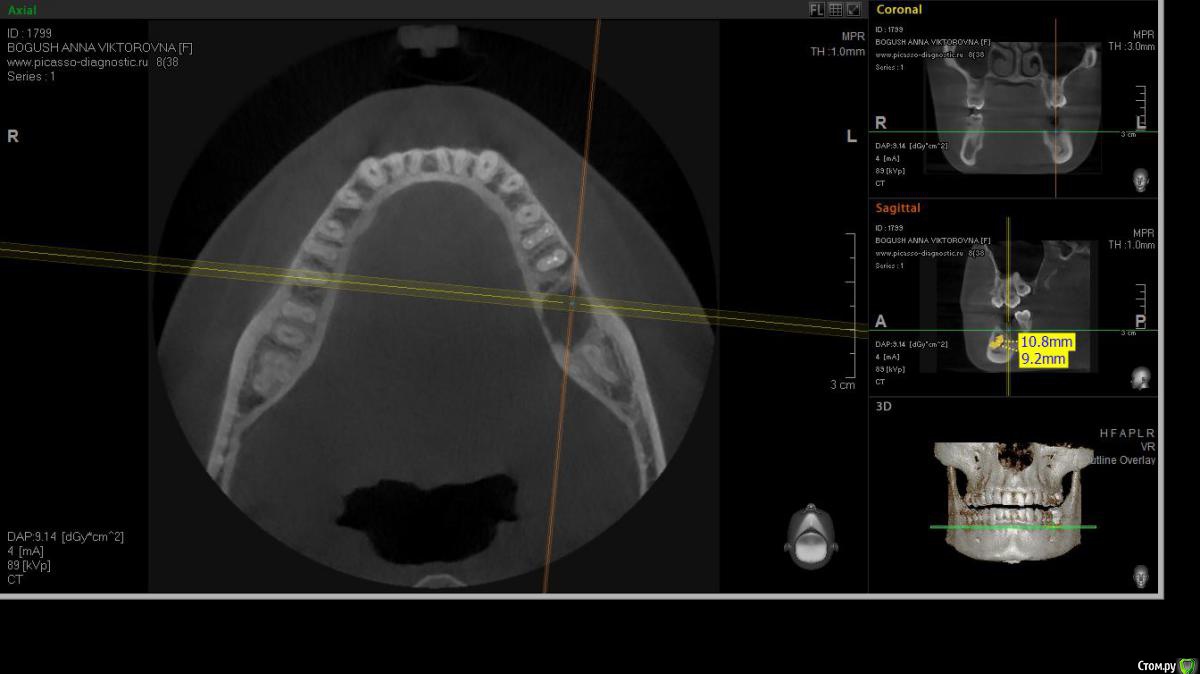

cor Опубликовано 2 апреля, 2016 Поделиться Опубликовано 2 апреля, 2016 Доброго времени суток, коллеги! Каков Ваш прогноз? Удалять пац. совсем не хочет(знакомая). Есть хоть какая то вероятность, что ретрит поможет? <script> </script> Ссылка на комментарий

cor Опубликовано 2 апреля, 2016 Поделиться Опубликовано 2 апреля, 2016 (изменено) гадская вирусятина на компе мешает. Нет конечно желающих. Но если ретрит будет, то делать его буду я. Но слабо верю в положительный исход(( Изменено 2 апреля, 2016 пользователем cor Ссылка на комментарий

St. Опубликовано 3 апреля, 2016 Поделиться Опубликовано 3 апреля, 2016 Доброго времени суток, коллеги! Каков Ваш прогноз? Удалять пац. совсем не хочет(знакомая). Есть хоть какая то вероятность, что ретрит поможет? Вполне есть смысл попробовать. Вероятность есть, только "заживать" будет долго. Ссылка на комментарий

cor Опубликовано 5 апреля, 2016 Поделиться Опубликовано 5 апреля, 2016 Почему?Наверное потому что такие объемные очаги ещё не перилечивал. Но деваться некуда, будем пробовать. Ссылка на комментарий

Л Ю С Я Опубликовано 5 апреля, 2016 Поделиться Опубликовано 5 апреля, 2016 Наверное потому что такие объемные очаги ещё не перилечивал. Но деваться некуда, будем пробовать.Уже не раз писали, что размер не имеет значения)))). Не надо перелечивать очаг. Ваша задача пройти, правильно сформировать, очистить и запаковать каналы, а также правильно восстановить коронковую часть. И будет вам хилинг))) 2 Ссылка на комментарий